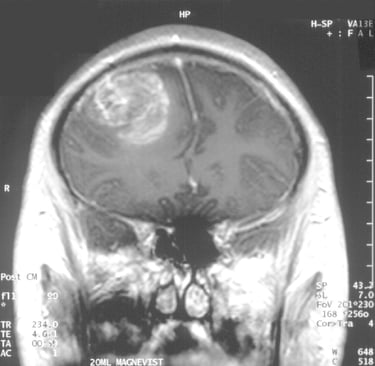

Çalışmanın Odak Noktası: Calgary Üniversitesi araştırmacıları, en agresif beyin kanseri türü olan glioblastomaya karşı, standart tedaviye (ameliyat, radyasyon, kemoterapi) ek olarak yüksek doz B3 vitamini (niasin) kullanımını araştırmaktadır.

Erken Dönem Sonuçları: 24 hasta ile yürütülen klinik denemelerin ilk aşaması oldukça olumludur. Hastaların %82'sinde 6 ay sonrasında hastalığın ilerlemediği görülmüştür. Bu oran, önceki standart tedavi verilerine kıyasla %28'lik dikkate değer bir iyileşme anlamına gelmektedir.

Uzman Uyarısı ve Süreç: Dr. Gloria Roldan Urgoiti ve Dr. Wee Yong gibi uzmanlar, yüksek doz vitamin tedavisinin ciddi yan etkileri olabileceğinden kesinlikle sıkı bir tıbbi gözetim altında yapılması gerektiği konusunda uyarmaktadır. Çalışmanın nihai ve kesin analizinin 2026 sonu veya 2027 başlarında tamamlanması planlanmaktadır.